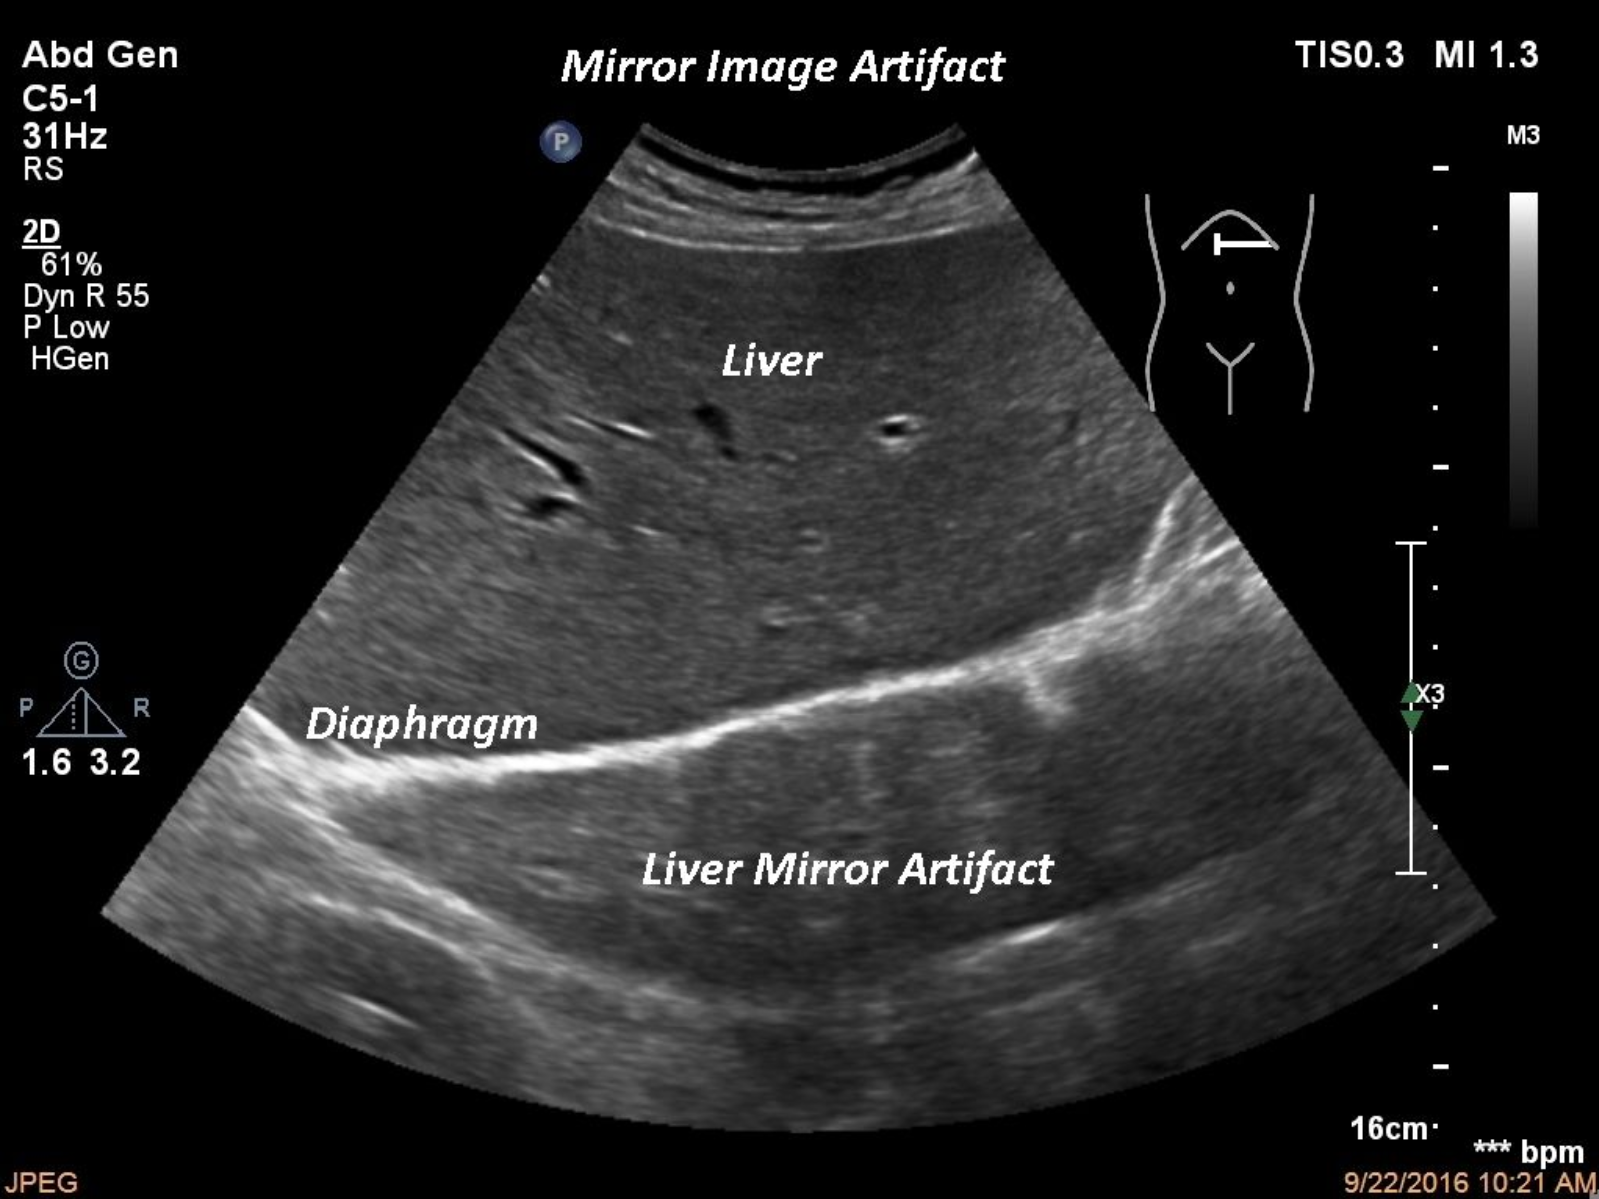

TITLE:   Mirror artifact

One of the most frequent ultrasound artifacts is the” mirror artifact”. In our case, in a slim patient the diaphragm acted as a mirror creating a false image above the diaphragm.

normal liver, artifact, mirror